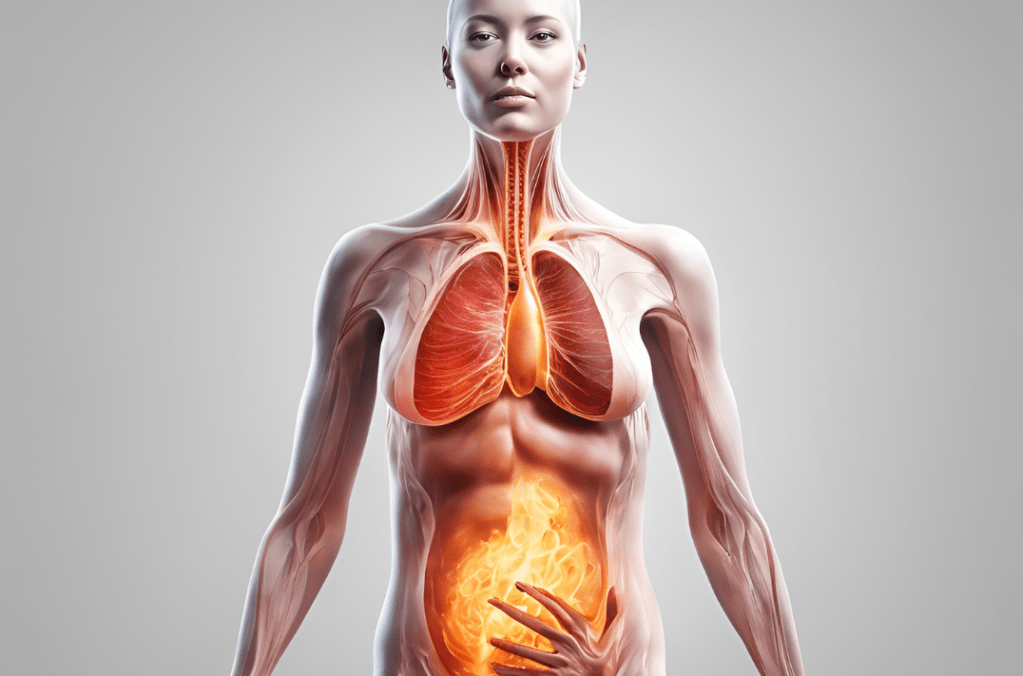

La inflamación crónica es tan frecuente hoy en día que las enfermedades degenerativas son la primera causa de morbilidad y mortalidad en todo el mundo. Y esta empeorando… hay muchas investigaciones que demuestran que las condiciones de la salud impondrán una carga aún mayor en el futuro.

Debido a la forma en la que vivimos en la actualidad, la inflamación crónica se presenta en casi todos los adultos y en un número creciente de adolescentes.

Como bien comentaba en anteriores artículos la inflamación crónica es en muchas ocasiones una inflamación silenciosa que no siempre presenta síntomas claros, pero hay señales y pruebas que pueden ayudar a identificarla:

- Síntomas Persistentes: En muchas ocasiones los síntomas pasan desapercibidos al ser normalizados en nuestra sociedad. Os pongo dos ejemplos, en ocasiones tras una comida nos sentimos muy hinchados, con muchas flatulencias e incluso calambres abdominales que se repiten con cierta frecuencia, o épocas en las cuales nos sentimos muy cansados, con falta de energía e incluso dolores de las articulaciones. Estas situaciones pueden ser una señal de que existe una inflamación crónica de base. Por tanto, estudiar los posibles síntomas es de vital importancia.